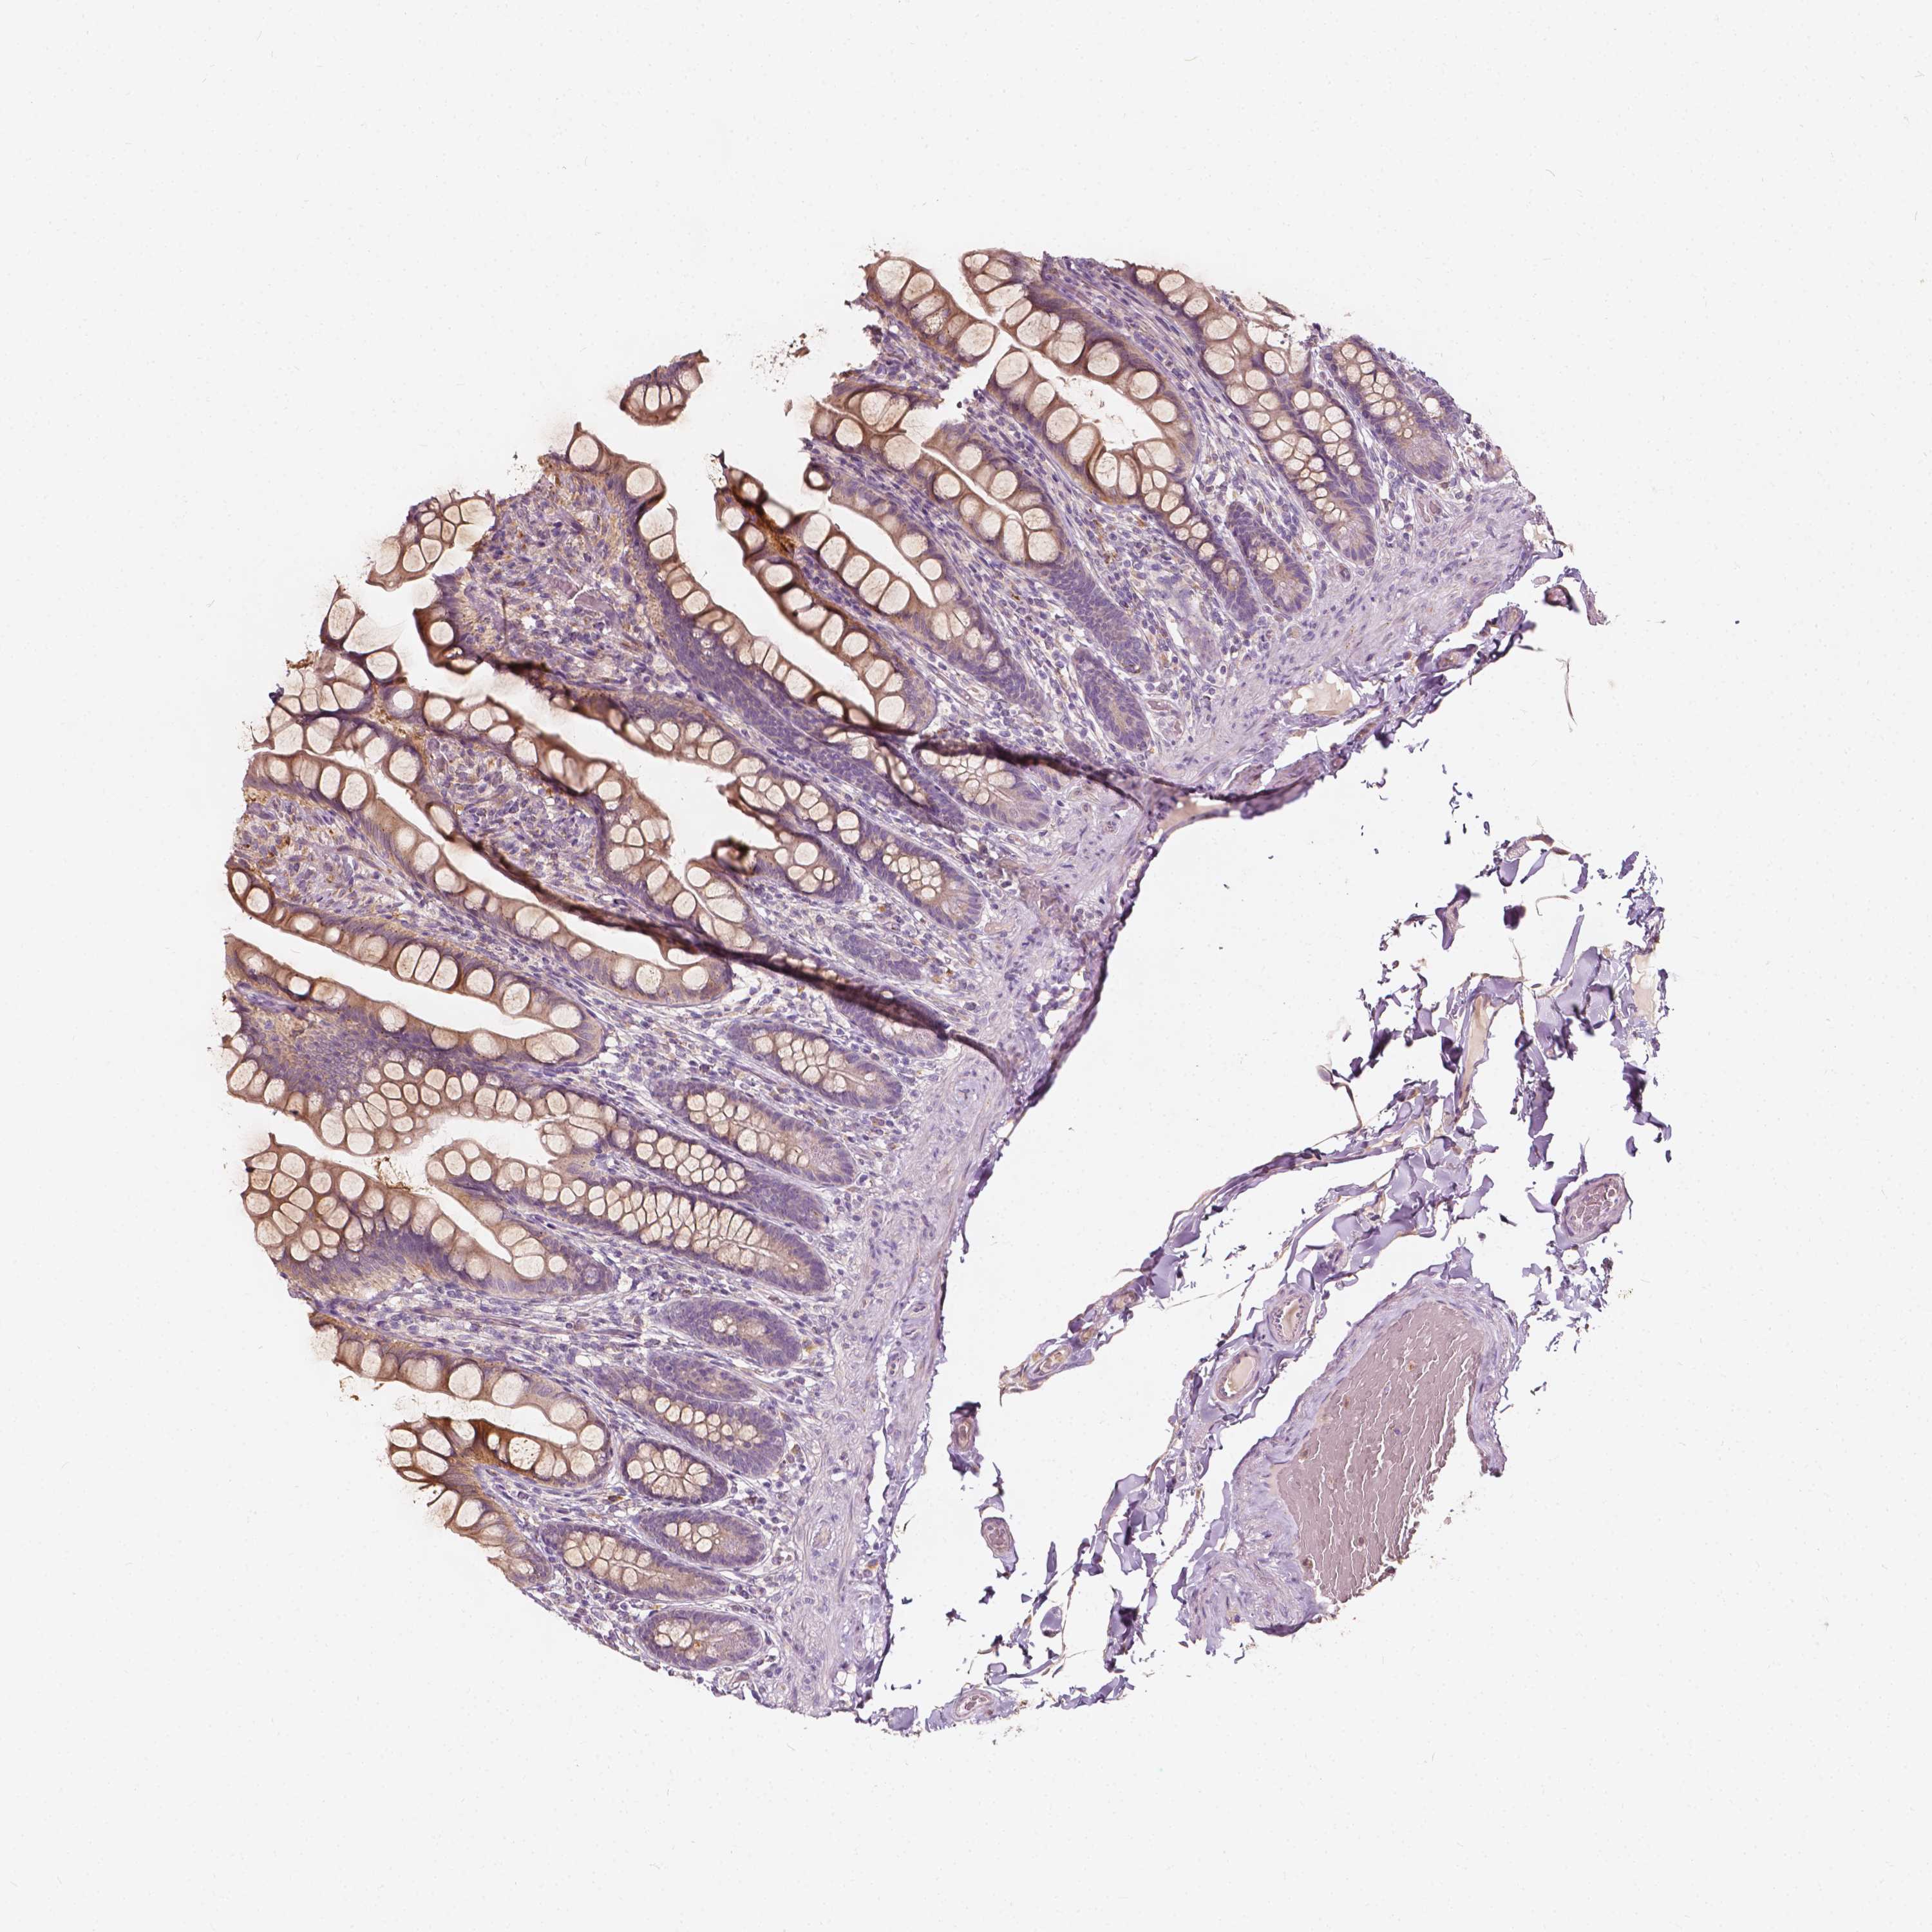

SMALL INTESTINE